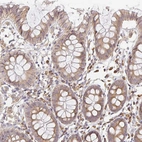

Immunohistochemical staining of human colon shows moderate cytoplasmic positivity in glandular cells.